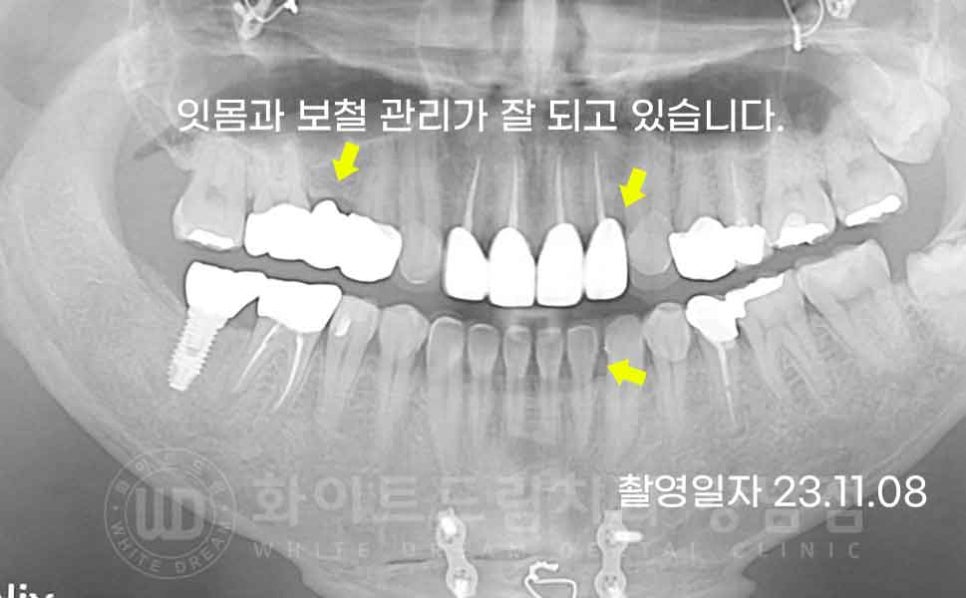

작년 11월에 1년 정기 체크와 스케일링 진료를 받으러 오셨는데요.

당시에도 보철 상태가 아주 양호하고 잇몸 관리도 열심히 해주셔서

초기 내원 당시보다 잇몸 상태도 많이 좋아지셨답니다.